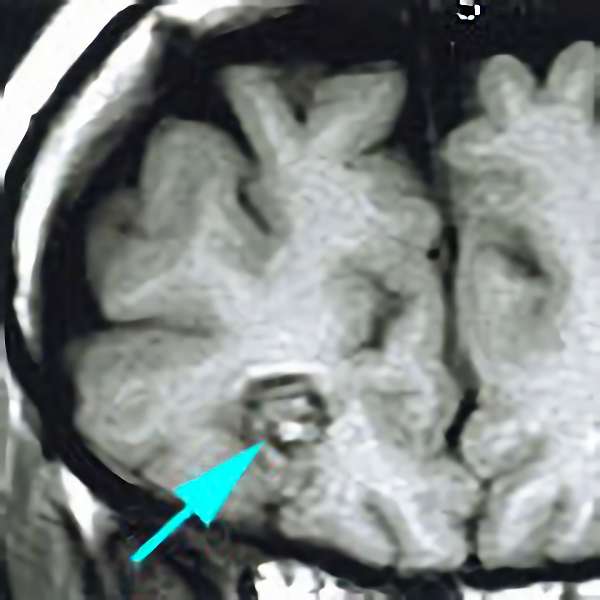

'19年11月

40代

富永

南田

基底核

海綿状血管腫

出血性

兵庫県の病院

より紹介

No.No.32 手術前1

No.No.32 手術前2

CT/MRにより完全に摘出されたことが確認された